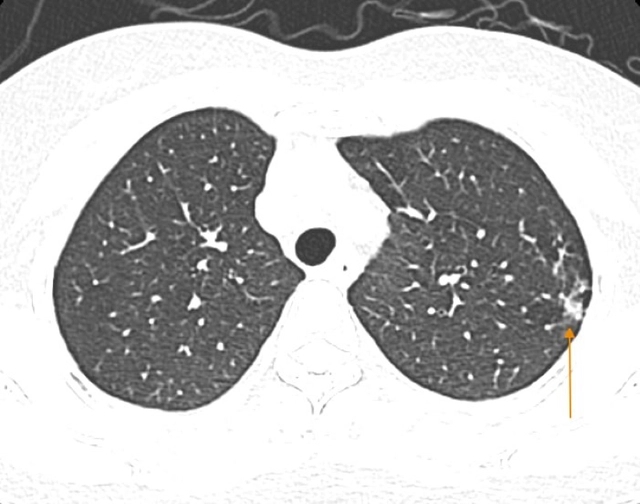

Hình ảnh chụp cắt lớp vi tính phổi phát hiện tổn thương. Ảnh: BVCC.

Hình ảnh chụp cắt lớp vi tính phổi độ phân giải cao cho thấy hình ảnh dày thành phế quản hai phổi kèm tổn thương kính mờ, nốt đặc, dày tổ chức kẽ thùy trên phổi trái.